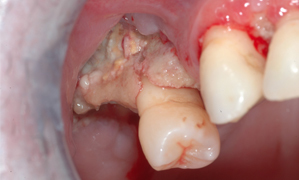

Osteoradionecrosis

Risk is highest –> Local surgical procedure is performed within 3 weeks of therapy or within 1 year of therapy

Not painful – does not affect the periosteum (most nerve sensation)

Treatment of Osteoradionecrosis

ABX

Debridement

Irrigations

Removal of diseased bone